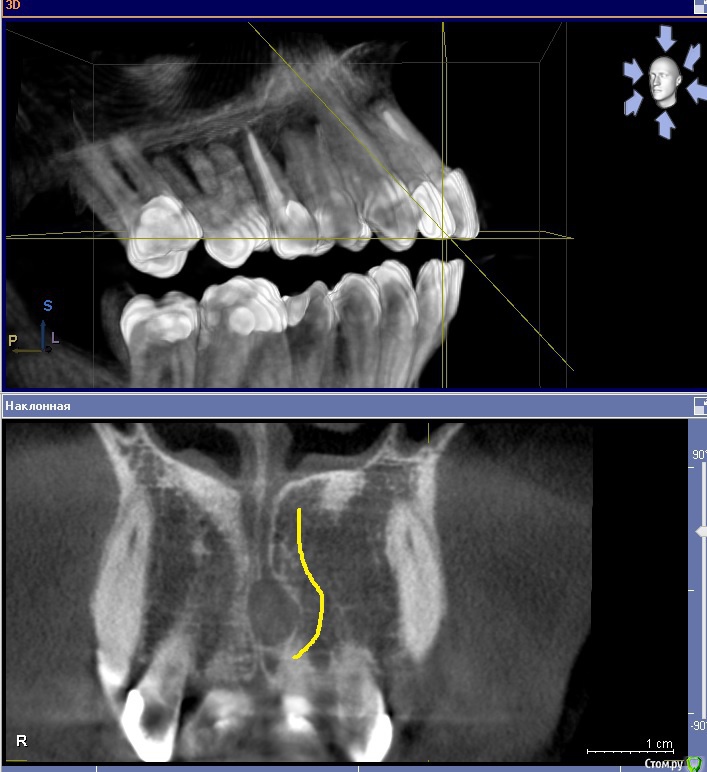

sergei995 Опубликовано 27 марта, 2016 Поделиться Опубликовано 27 марта, 2016 (изменено) Здравствуйте! Проконсультируйте, пожалуйста. В 2006м году у меня на небе ровно по центру образовалась небольшая припухлость, которая пару дней болела. Я сходил к врачу, сделал рентген - все было в норме. Посоветовали пополоскать и всё. Так я и сделал, болезненность прошла, но легкая выпуклость в этом месте осталась, которая совершенно не беспокоила. Пару раз только за 10 лет, когда простывал, это место становилось чуть болезненным (на день). Недавно сделал КТ (по другому вопросу - планирую имплантацию 6ки). И вот такая картинка получилась. Мне сказали, что это место - место "резцового отверстия". И действительно, у меня там там присутствует некоторое образование. Нужно ли что-то с этим делать? Нужно ли иссекать и дренировать эту "полость" (видимо, это полость)? (Мой врач предлагает пока просто наблюдать) При этом слизистая нёба не изменена, отечность отсутствует. Насморками и гайморитами не страдаю вообще. Прикладываю результаты КТ - два наиболее характерных среза. Заранее благодарю за помощь! Изменено 27 марта, 2016 пользователем sergei995 Ссылка на комментарий

___49___ Опубликовано 28 марта, 2016 Поделиться Опубликовано 28 марта, 2016 Очень похожа на кисту резцового канала, образование не злокачественное, а доброкачественное, растет медленно рассасывая окружающую кость , при определенных условиях может нагноится. Лучше убрать хирургически в плановом порядке с последующим не продолжительным ношением защитной небной пластинки. 1 Ссылка на комментарий

Doctor Vlad Опубликовано 29 марта, 2016 Поделиться Опубликовано 29 марта, 2016 Размер не большой, возможно киста резцового канала! я б понаблюдал. периодически контроль роста. при обострении провести диагностическую пункцию на наличие кистозной жидкости Ссылка на комментарий